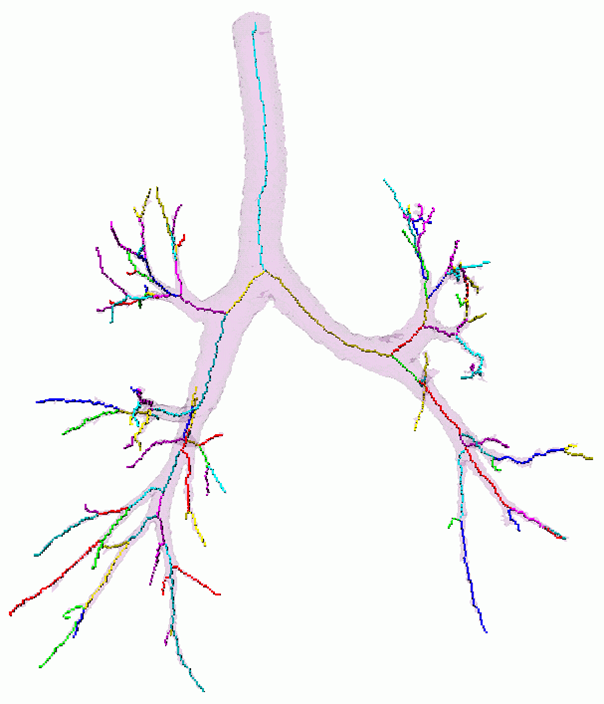

The key steps are now illustrated:

Segmentation - adaptive region growing (left), extracting centerlines - topologically and geometrically correct thinning (middle), and excluding branch-areas based on 3D distance map calculation (right).

Partitioning centerlines in a formal tree data structure (left), partitioning segmented tree via isotropic label propagation (middle), and quantitative analysis formal XML tree with associated measurements (right).